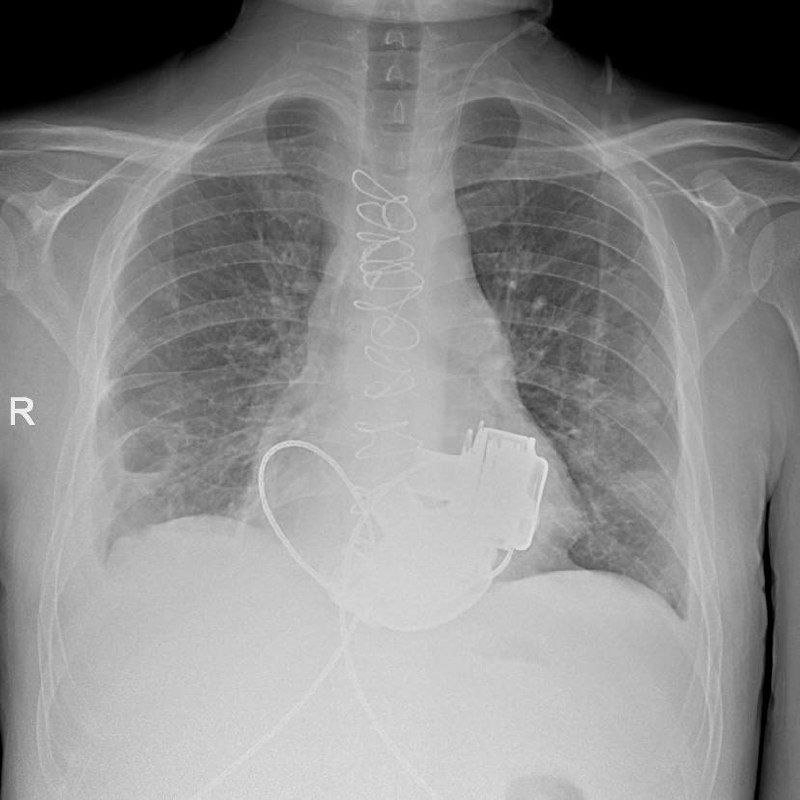

Рентген пациента с искусственными желудочками сердца. Фото: Телеграм-канал Маринской больницы

В Мариинской больнице готовится к выписке уникальный пациент, который с недавних пор живет без пульса. Как сообщает учреждение в своем телеграм-канале, в конце ноября 2025 пациенту впервые в России имплантировали сразу два искусственных желудочка сердца. Когда мужчина поступил в больницу, показатели работы его сердца были такими, "будто человек уже не жив, а мертв". При этом из-за ряда осложнений трансплантация целого сердца была невозможной. Главный врач больницы Игорь Реутский принял решение об имплантации искусственных желудочков. Операция продолжалась около 4 часов.